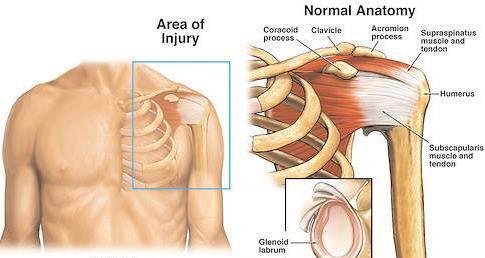

Skulderen omfatter krageben, skulderblad og overarmsben, samt muskler, sener og leddbånd. Foran i skulderen går kragebenet fra brystbenet og til en utstikkende del av skulderbladet ytterst (lateralt) mot skulderleddet. Mellom kragebenet (clavicula) og skulderbladkanten/ytre del av skulderbladet (acromion) er et uekte ledd –Acromioclavicularleddet (AC-leddet).

Selve skulderleddet er et kuleledd hvor overarmsbenet møter en leddflate på skulderbladet. Det er et komplisert ledd med stor bevegelsesfrihet, relativt liten stabilitet og ganske romslig leddkapsel.

Skjer oftest fremover (90-95%), fordi det først og fremst er muskler som hindrer at leddhodet forskyves

Normal struktur i skulder To bilder av fremre luksasjon. Bilder tilpasset av Therese Dahl Kristensen